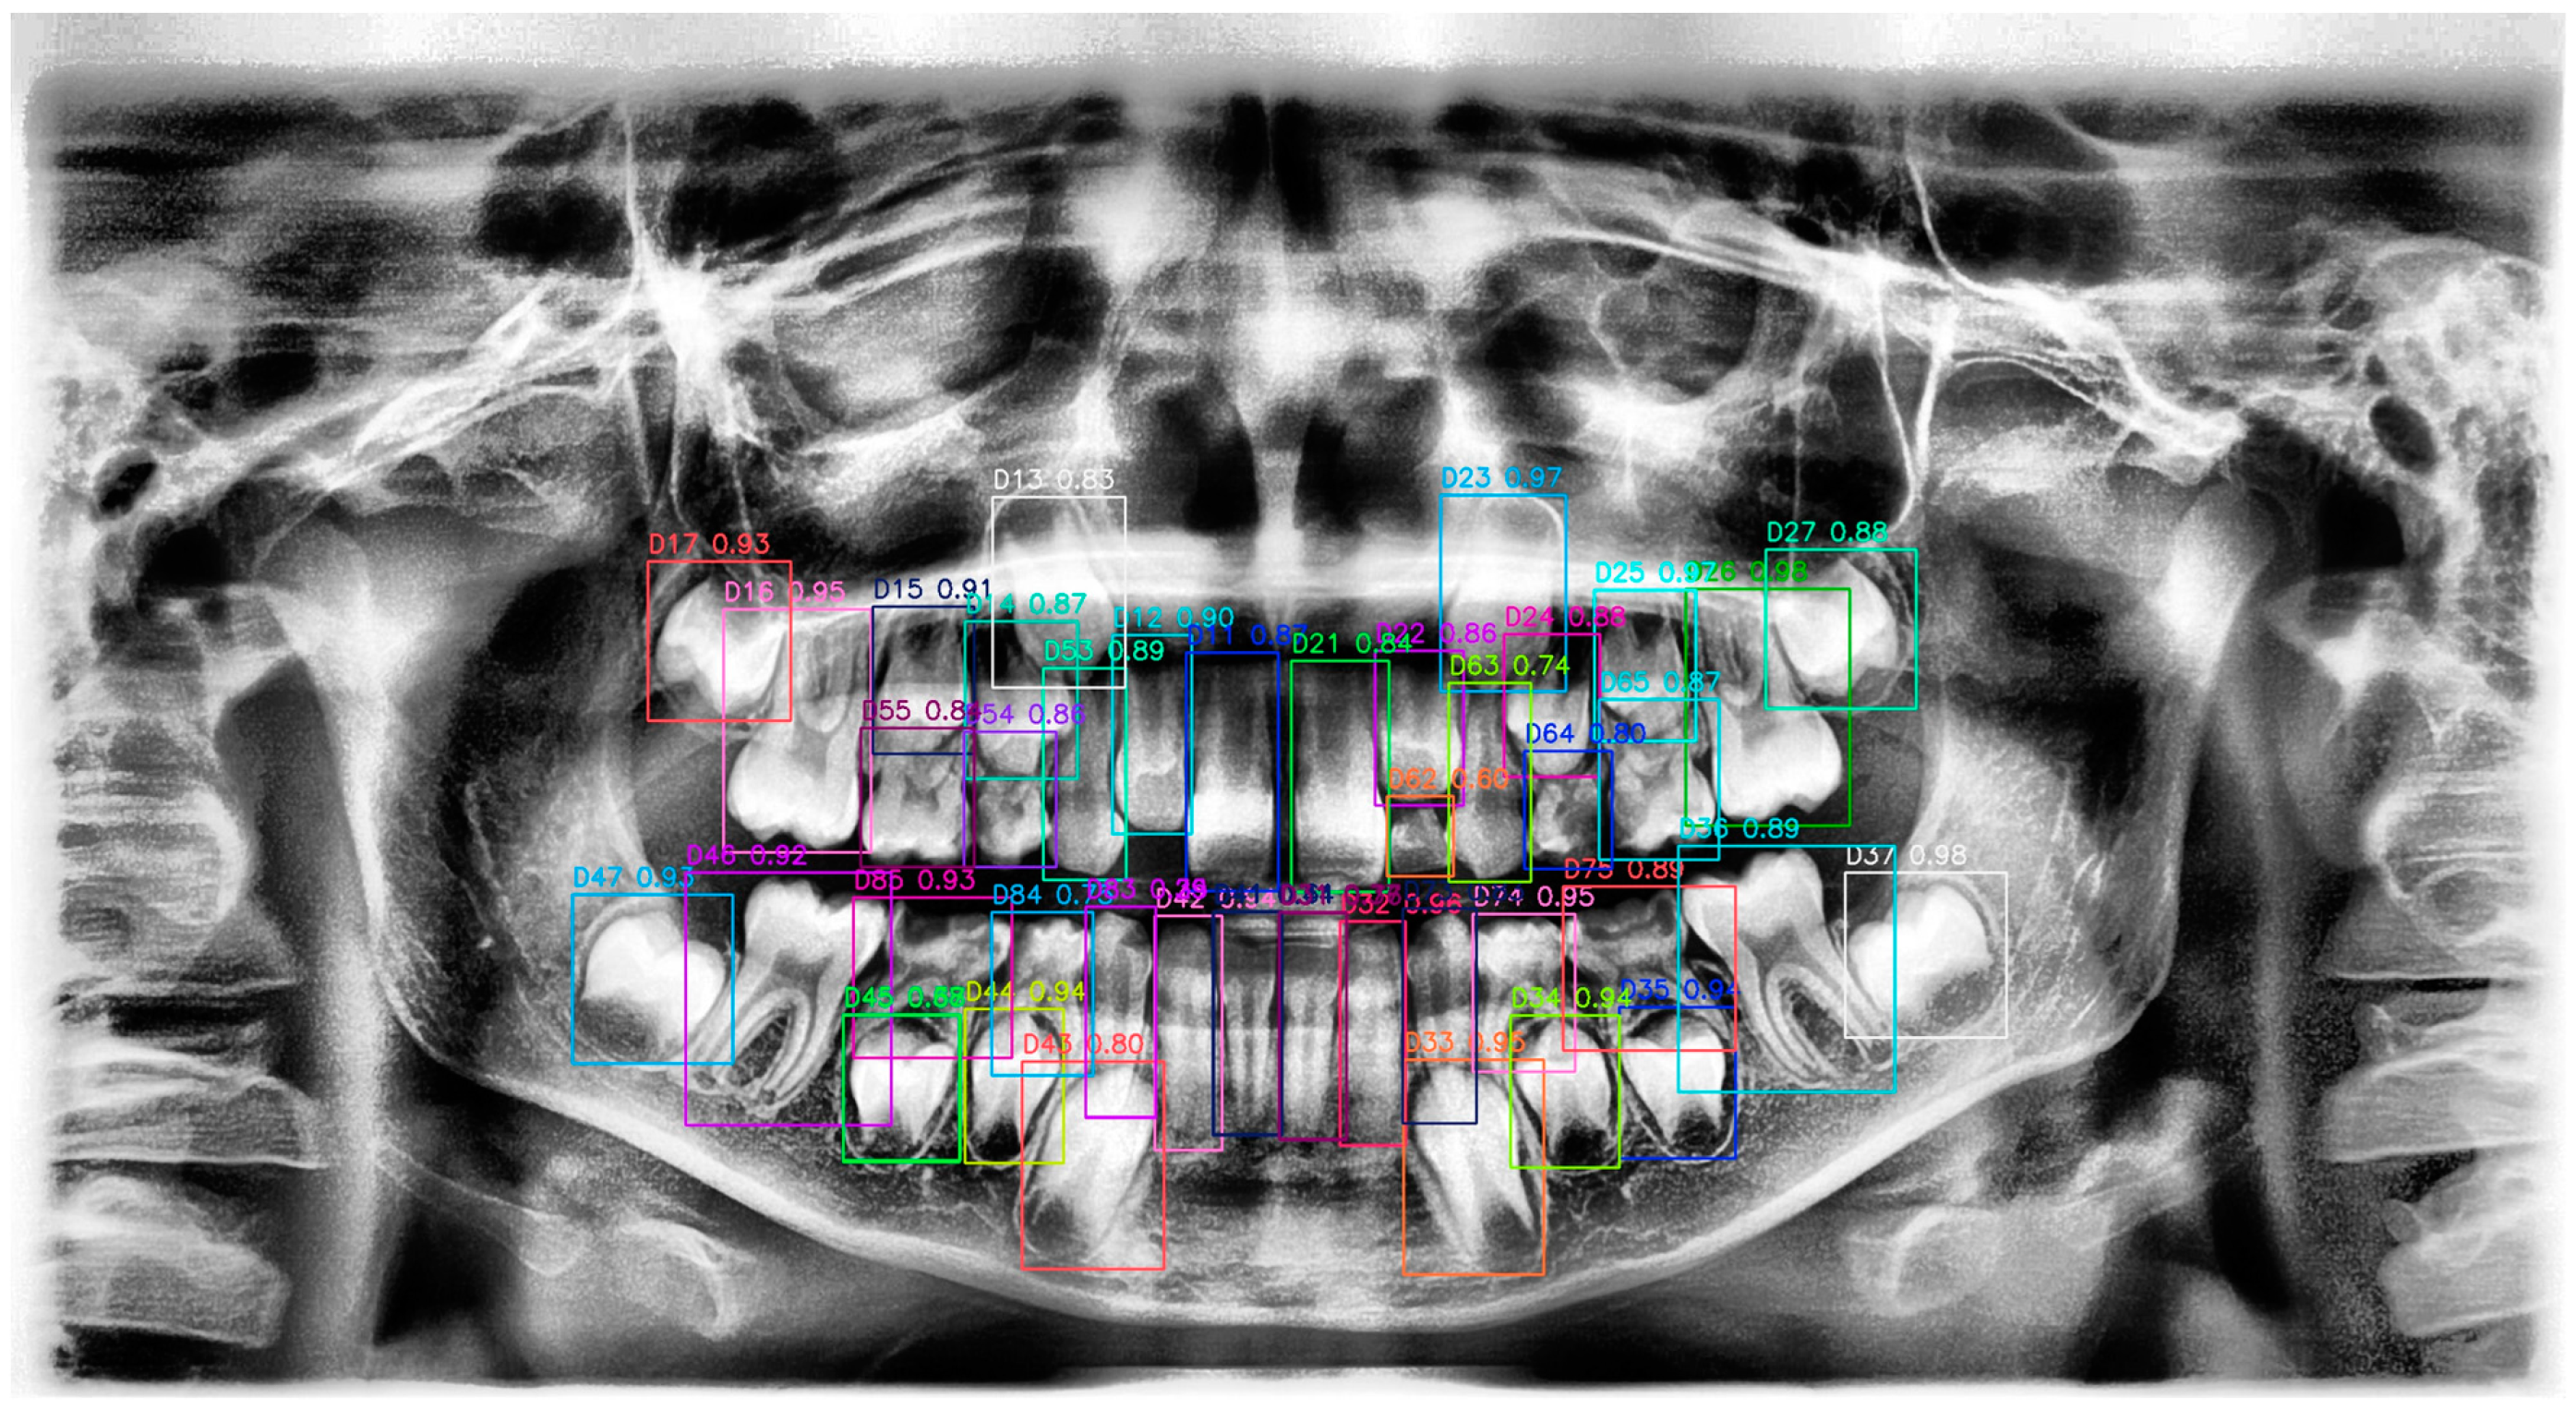

3. Results